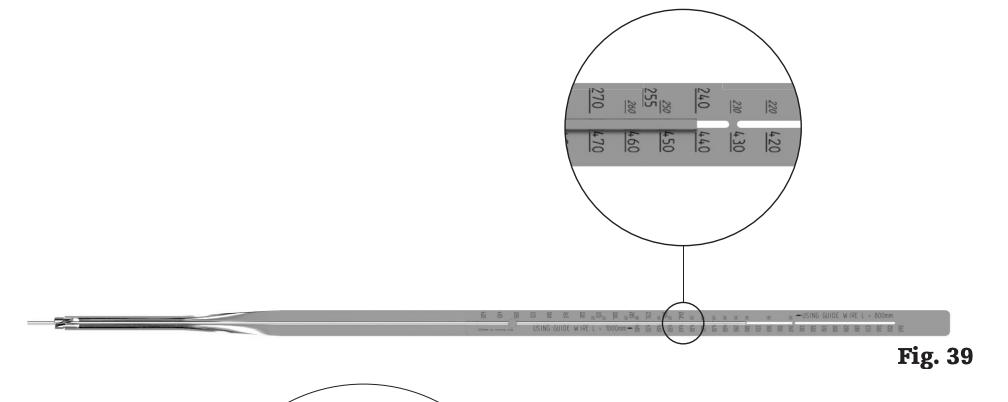

• length

• determine appropriate nail length by measuring the remaining length of the guide wire

• confirm the position of the tip of the guide wire prior to measurement

• ensure that the tip of the Guide Wire Ruler is fully seated on the bone prior to determining measurement

• if the measurement is between markings, use of the shorter nail is recommended